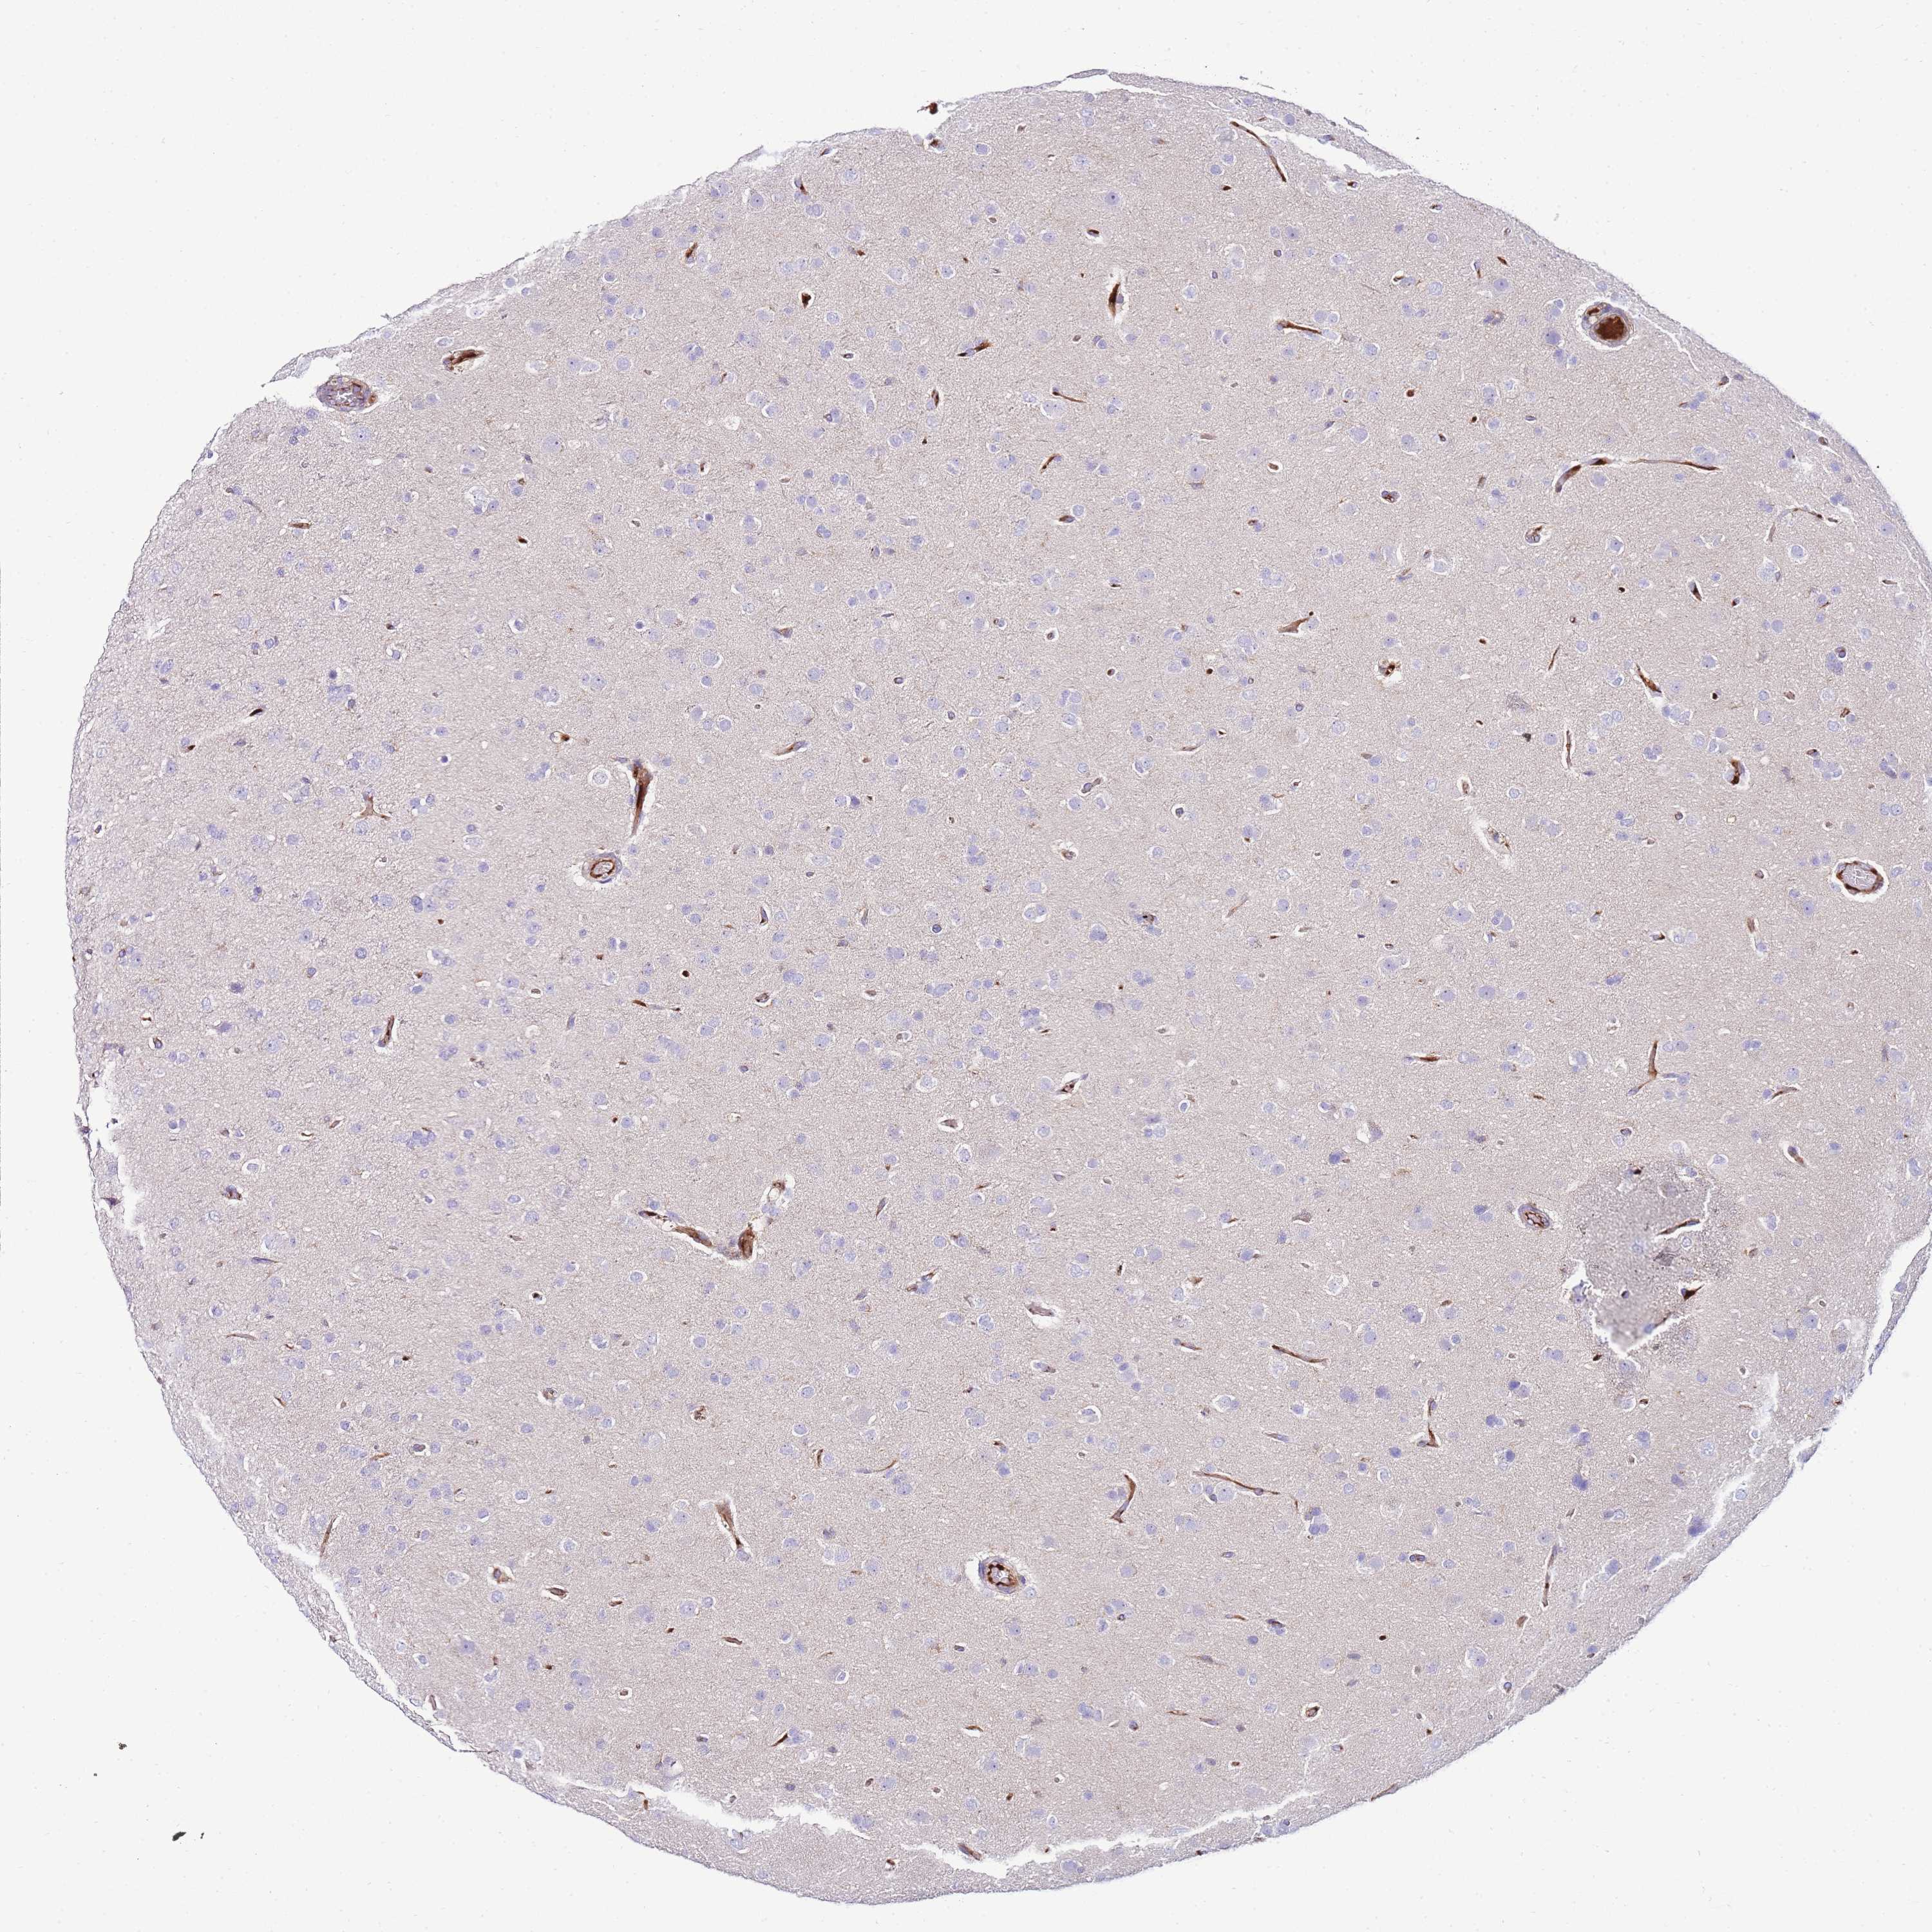

GLIOMA - Protein expressioni

A mouse-over function shows sample information and annotation data. Click on an image to view it in a full screen mode. Samples can be filtered based on level of antibody staining by selecting one or several of the following categories: high, medium, low and not detected. The assay and annotation is described here.

Note that samples used for immunohistochemistry by the Human Protein Atlas do not correspond to samples in the TCGA dataset.

Antibody stainingi

Antibody staining in the annotated cell types in the current human tissue is reported as not detected, low, medium, or high, based on conventional immunohistochemistry profiling in selected tissues. This score is based on the combination of the staining intensity and fraction of stained cells.

Each image is clickable and will lead to virtual microscopy that enables deeper exploration of all samples and also displays staining intensity scores, fraction scores and subcellular localization as well as patient and tissue information for each sample.

Antibody HPA049482

Staining

High

Medium

Low

Not detected

Intensity

Strong

Moderate

Weak

Negative

Quantity

>75%

75%-25%

<25%

None

Location

Nuclear

Cytoplasmic/membranous

Cytoplasmic/membranous,nuclear

Glioma, malignant, High grade

Glioma, malignant, Low grade